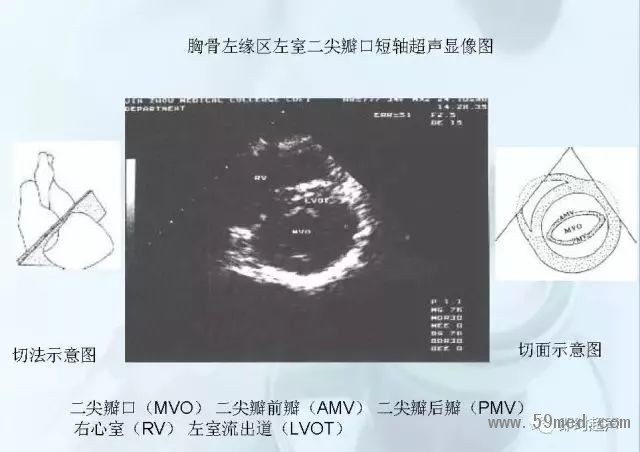

新聞中心 收藏!正常B超解剖圖譜,超實用!